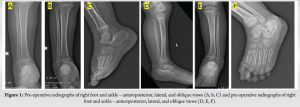

A 3-year-old girl presented to the emergency department of our tertiary care center with bilateral foot pain following an alleged fall from a height of approximately 30 feet. On physical examination, there was generalized swelling and tenderness over the dorsal aspect of both mid-feet, the heel of the left foot, and the forefoot on the right side. Movement of the foot and ankle was painful bilaterally, and the child was unable to bear weight, even after administration of weight-based analgesics. Further examination was limited due to reduced compliance secondary to pain and distress. Radiographs and computed tomography (CT) scans were obtained (Fig. 1-3), confirming the multiple injuries. In the left foot – closed distal tibial physeal injury (Salter Harris Type 2 Injury), distal fibular physeal injury (Salter Harris Type 2), talus fracture (Hawkins Type 1) and calcaneum fracture (Schmidt and Weiner Type 5) without distal neurovascular deficit (DNVD) and in the right foot – closed fractures of the 1st and 2nd metatarsal base (Lisfranc Disruption-Hardcastle and Meyerson Type B1), base of the 3rd and 4th metatarsals; shaft of the 4th and 5th metatarsals; and talus fracture (Hawkins Type 1) without DNVD. Following initial stabilization according to advanced trauma life support protocol, bilateral below-knee slab immobilization was applied.